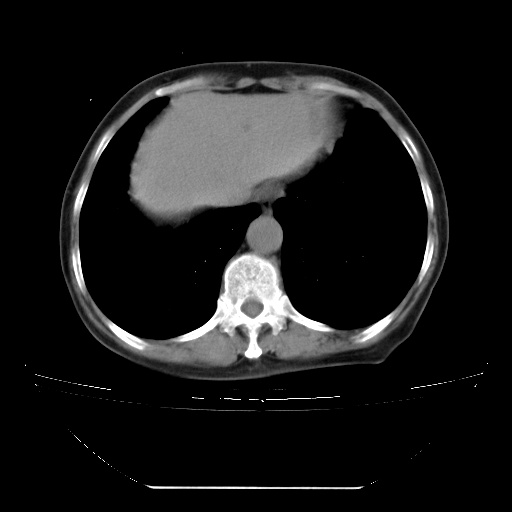

查原发灶吧,肺内转移瘤!肝内也有病灶,需强化明确。

以下是引用zsl6918在2009-3-5 23:00:00的发言:[br]查原发灶吧,肺内转移瘤!肝内也有病灶,需强化明确。

两肺内病灶呈小结节状和树芽状,纵膈的肿大的淋巴结密度不均匀,并见有钙化,多形态病灶,考虑为两肺结核,肝内考虑小囊肿。

以下是引用zhw974247在2009-3-6 6:25:00的发言:[br]两肺内病灶呈小结节状和树芽状,纵膈的肿大的淋巴结密度不均匀,并见有钙化,多形态病灶,考虑为两肺结核,肝内考虑小囊肿。